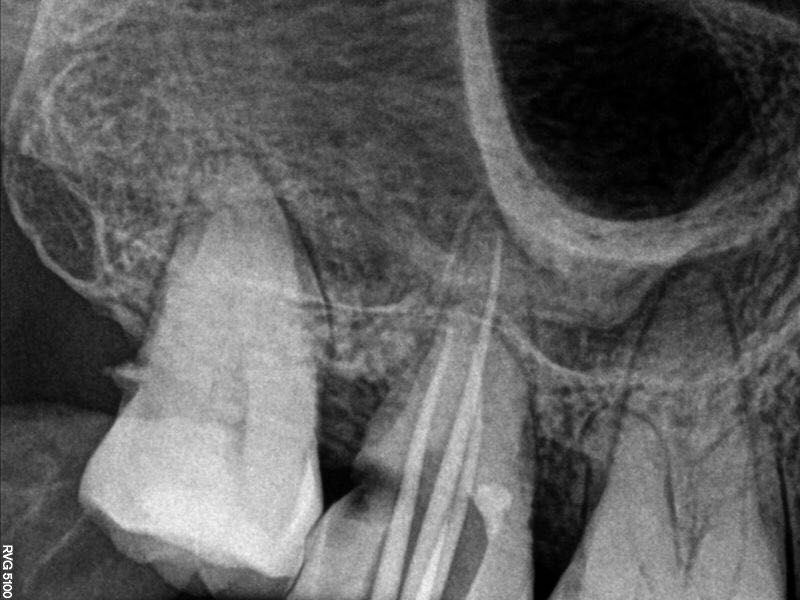

行17牙局麻下开髓失活,两周复诊,去封后见髓腔内大块髓石,p5超声去除大块髓石,根管口完全堵塞,继续去除髓石致近中壁侧穿

行近中壁侧穿修补,之后在显微镜下ET20暴露根管口,三根,均行疏通,扩锉根充